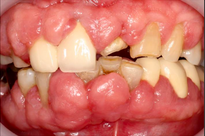

Case Background

A 65-year-old female on antihypertensives and immunosuppressants presented with severe gum swelling, inability to chew, and difficulty maintaining oral hygiene. This led to multiple decayed and periodontally compromised teeth, worsening her overall condition.

Drug-influenced gingival overgrowth or ‘DIGO’ in short, manifests as abnormal swelling of the gingiva.

- The condition is usually caused by adverse reactions to certain drugs such as antihypertensives, anticonvulsants or immunosuppressants.

- As the gum tissues become significantly larger, it may impede normal masticatory function, daily oral hygiene, and aesthetics, severely diminishing one’s quality of life. (Sabarudin et al. 2022)

Before Treatment